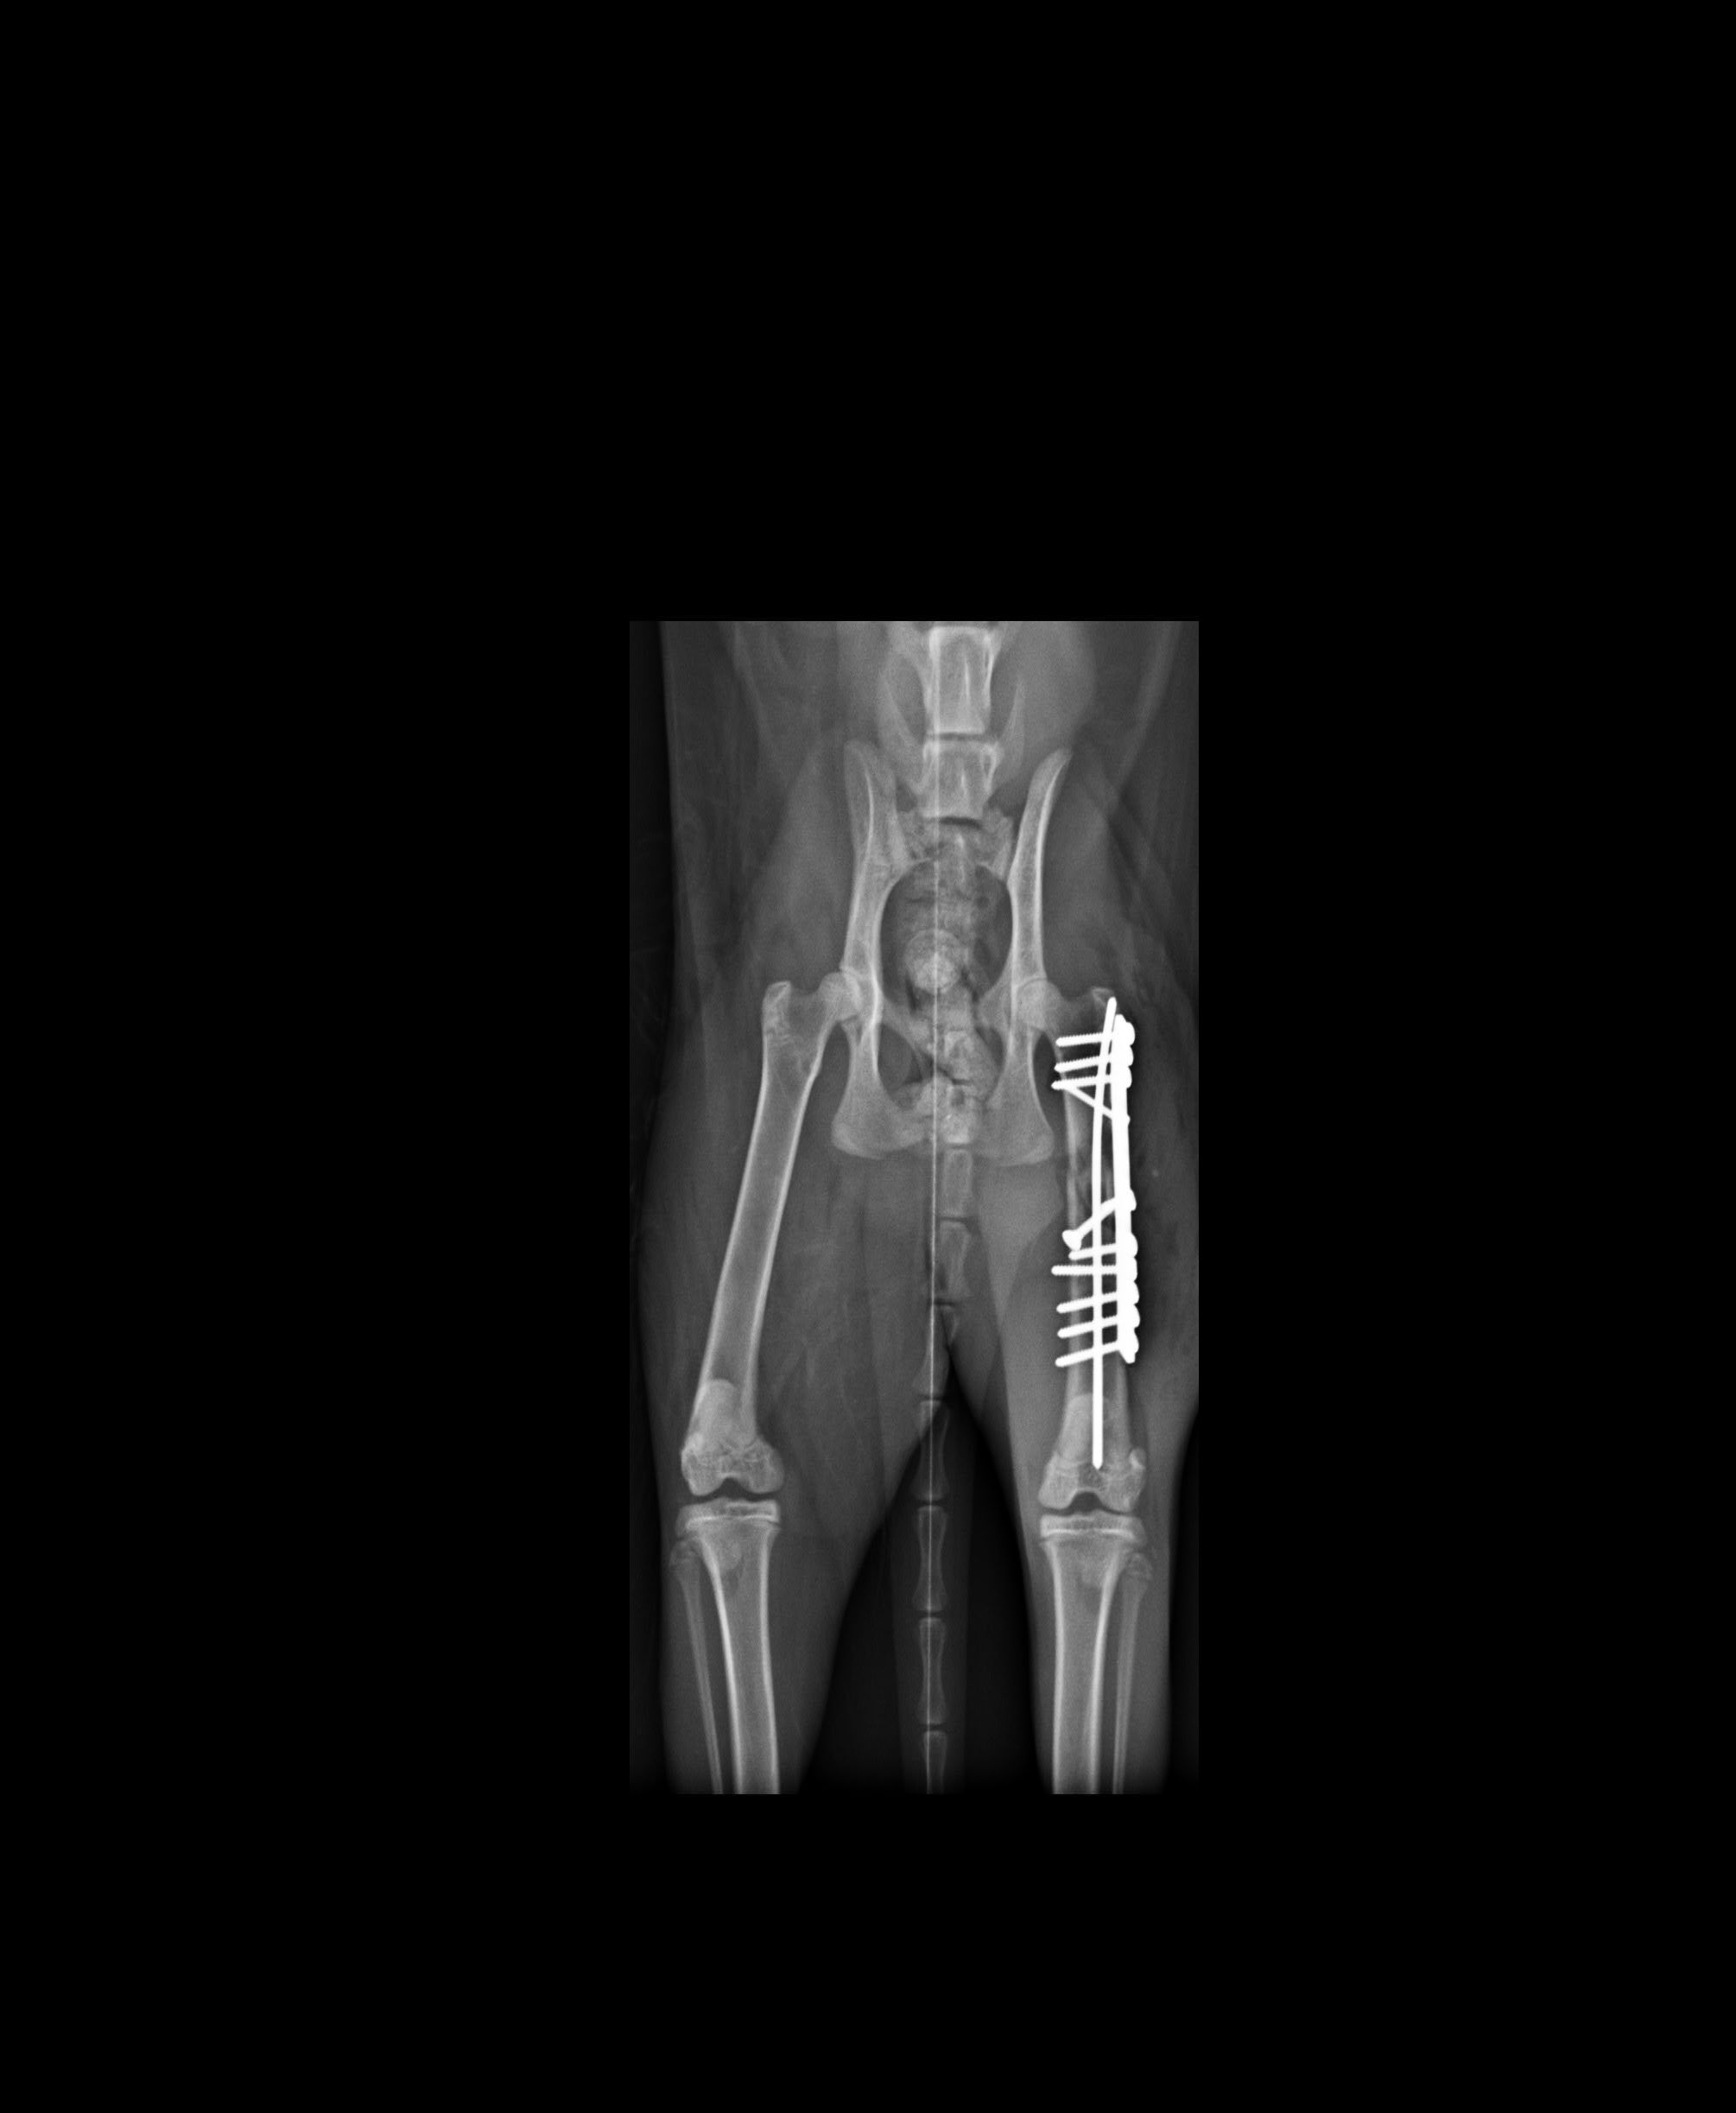

主題: 車禍貓咪 申請者姓名: 周筱珮 花色: 申請日期: 2016-04-21 00:35:39 申請者部落格: 申請者臉書網址: 所在縣市/合作醫院: 高雄市/恩澤動物醫院 治療費用: 33700元 需求人數: 35人 已結案 (2024-06-01 13:37:03) 報名人員: 張嘉琪(已付款)、Egg Chuang(已付款)、捲捲(已付款)、王琇盈(已付款)、Win Chih Chen(已付款)、家有三色喵(已付款)、nicca(已付款)、SW(已付款)、Po-Lin Chen x2(已付款)、JJ(已付款)、Kuo Wei(已付款)、Kuo Wei、Ruby(已付款)、陳昱先(已付款)、Amber Chung(已付款)、諾小弟(已付款)、mmaormio(已付款)、Alice Tsai(已付款)、Summer(已付款)、Irene Hu(已付款)、謝忻 x3(已付款)、Moon(已付款)、Joyce Yeh(已付款)、Eric Chien(已付款)、陳千歲(已付款)、rainbowstar39(已付款)、老貓奴(已付款)、misselaine(已付款)、Celine(已付款)、Ivy Fu(已付款)、Emily(已付款)、Kate Kuo(已付款)、Li Yi Ting(已付款)、 候補人員: 動物病情說明: 已經結紮的街貓,一星期前突然不見,一直找尋不到,直到星期五出現,發現後腳沒法著地,行動很吃力,星期六誘捕帶到醫院做檢查,醫生說是開放性骨折,需要開刀,但醫療費用不低,我只是個家庭主婦沒有收入,想請協會幫忙救救她。目前醫院是說要儘快手術預計星期一動刀。 動物近況說明: 醫生說因大腿骨頭斷裂成4塊很碎無法只用鋼釘接回,醫生處理方式是在骨頭的前後端接上骨板,加上a扣年輕骨頭癒合能力會比較好,所以目前先暫定住院10天,在看後續狀況決定,我每天都有去看a扣食慾方面都還不錯,感覺精神也不錯,只是醫院給的估價費用已經超過3萬了,手術後的x光我等醫院給我在補上。

目前a扣今天出院已經帶回家照護,需要限制活動空間,讓大腿骨慢慢長回來,醫生預估一個月後可慢慢增加活動空間。